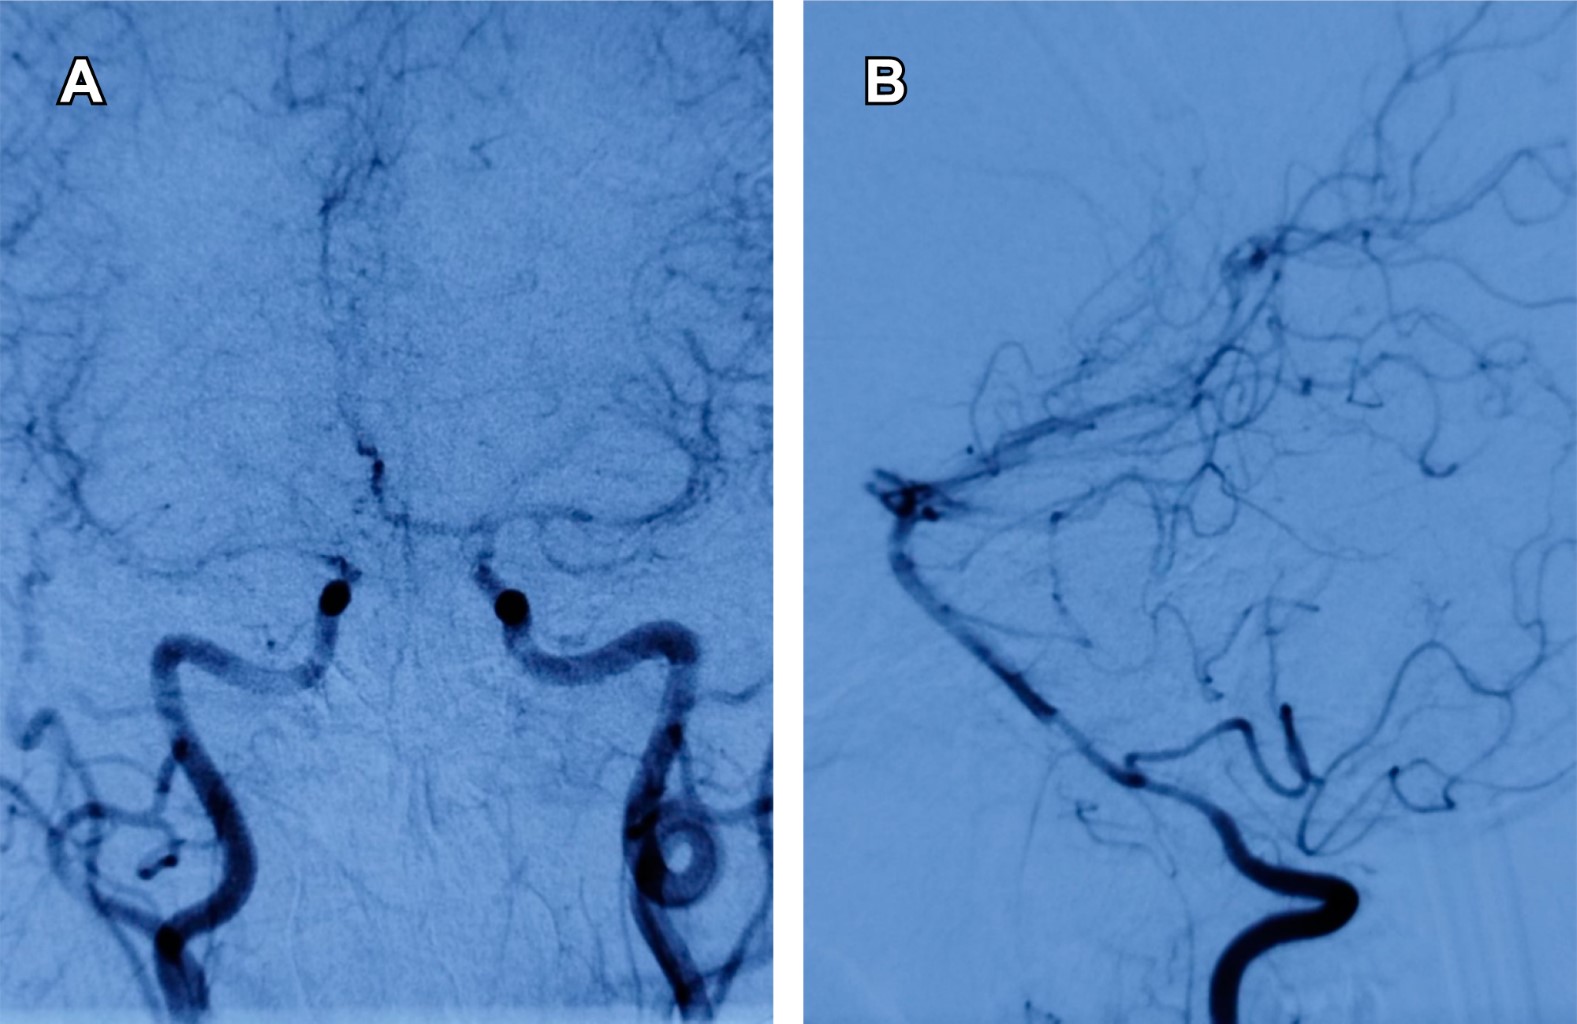

Introduction: primary vasculitis of the central nervous system (PVCNS) is rare, with heterogeneous clinical presentation. Case report: 35-years-old female with seven days with headache, without improvement with analgesics, adding vomiting and stupor, right hemiparesis, and aphasia; CT showed hemorrhages in the right caudate nucleus and left frontal lobe, laboratory tests including antibodies and acute phase reactants normal; pan-angiography showed: a pattern of vasculitis of trunk branches in cerebral arteries and occlusion of the inferior longitudinal sinus; with a diagnosis of possible PVCNS. Drainage of frontal hemorrhage and biopsy was performed, which confirmed the diagnosis; beginning treatment with methylprednisolone bolus and cyclophosphamide, obtaining clinical improvement. Conclusions: PVCNS presents heterogeneous clinical manifestations of acquired neurological deficits; it is a challenge. Its diagnosis implies the existence of the following: a) the acquired neurological deficit, unexplained by another cause, b) angiographic or histopathological evidence of PVCNS, c) absence of systemic vasculitis or other condition that explains it.

Figure 1